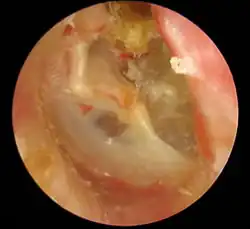

Die Diagnose wird mit Hilfe der Ohrmikroskopie gestellt. Der typische Befund ist ein Defekt in der Pars tensa oder Pars flaccida des Trommelfells mit Nachweis weißlich-gelber Schuppen oder Zellmassen in der Läsion. Nicht selten finden sich Polypen aus Granulationsgewebe. Untersucht man das Trommelfell durch die direkte Otoskopie, sieht man häufig eine Perforation des Trommelfells am oberen oder hinteren Rand.

Zumeist befindet sich das Cholesteatom am oberen, hinteren Teil der Paukenhöhle, so dass sich sein Detritus durch eine Perforation an der Pars flaccida des Trommelfells, seltener auch an der Pars tensa, dann aber am Rand nahe dem Faserring, Anulus fibrocartilagineus,[21] in den Gehörgang entleert.

- Chronische Knocheneiterung, auch chronische epitympanale Otitis media; hier handelt es sich um eine Form des Cholesteatoms. Beim Blick mit dem Otoskop auf das Trommelfell findet man dort, am Rande typischerweise einen Defekt, ferner sieht man weißliche Granulationen oder auch rote Pseudopolypen im Defekt.[17]